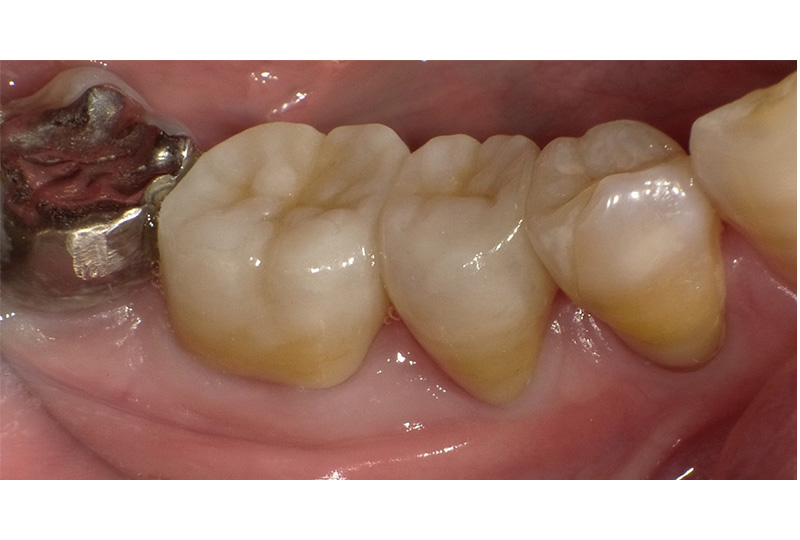

審美性にこだわった治療から保存が難しいと言われた歯の保存やお口全体をより良い状態にする一歩進んだ専門的な治療を行います。

『歯のひび(歯根破折)』など通常であれば抜歯と言われるような歯の保存や歯を失った所に親知らずなどを移動させる『歯の移植』など一般の歯科医院では行わない特殊な治療も行なっております。